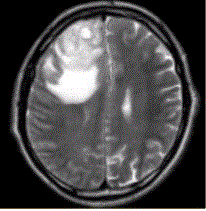

患者女,67岁,头痛伴呕吐1周。既往体健。MR表现如下图。临床拟诊为A.脑脓肿B.转移瘤C.成胶质胞瘤D.少枝胶质细胞瘤E.成髓细胞瘤

问题 患者女,67岁,头痛伴呕吐1周。既往体健。MR表现如下图。 临床拟诊为

选项 A.脑脓肿 B.转移瘤 C.成胶质胞瘤 D.少枝胶质细胞瘤 E.成髓细胞瘤

答案 C